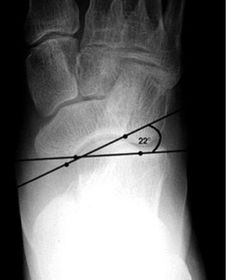

What angle is this? Is this normal or abnormal? | 1st intermetatarsal angle Abnormal. Greater than 9 degrees is abnormal. Usually due to metatarsus primus varus |